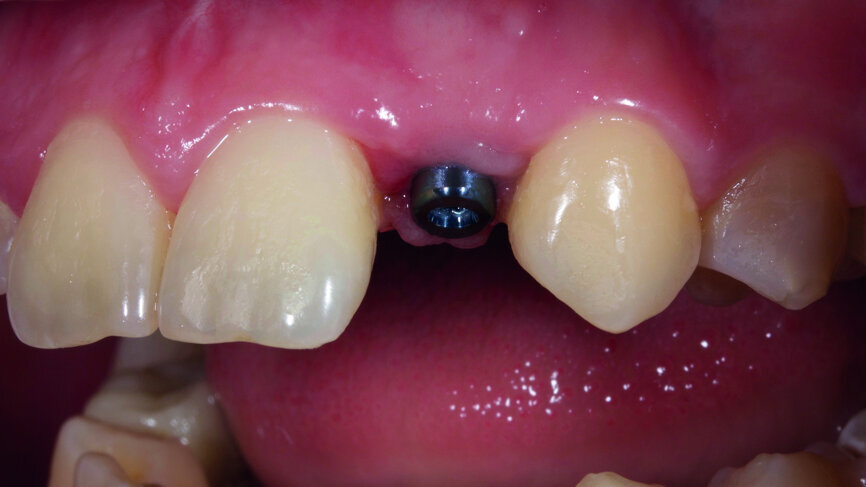

Fig. 6: Successful placement of the implant.

Fig. 7: Successful placement of the implant.

Thanks to digital planning and a carefully fabricated surgical guide, the implant was placed successfully, even though the anatomical conditions appeared to be less than advantageous. We achieved a torque of 30 Ncm and attached a healing abutment to the implant (Figs. 6 & 7).